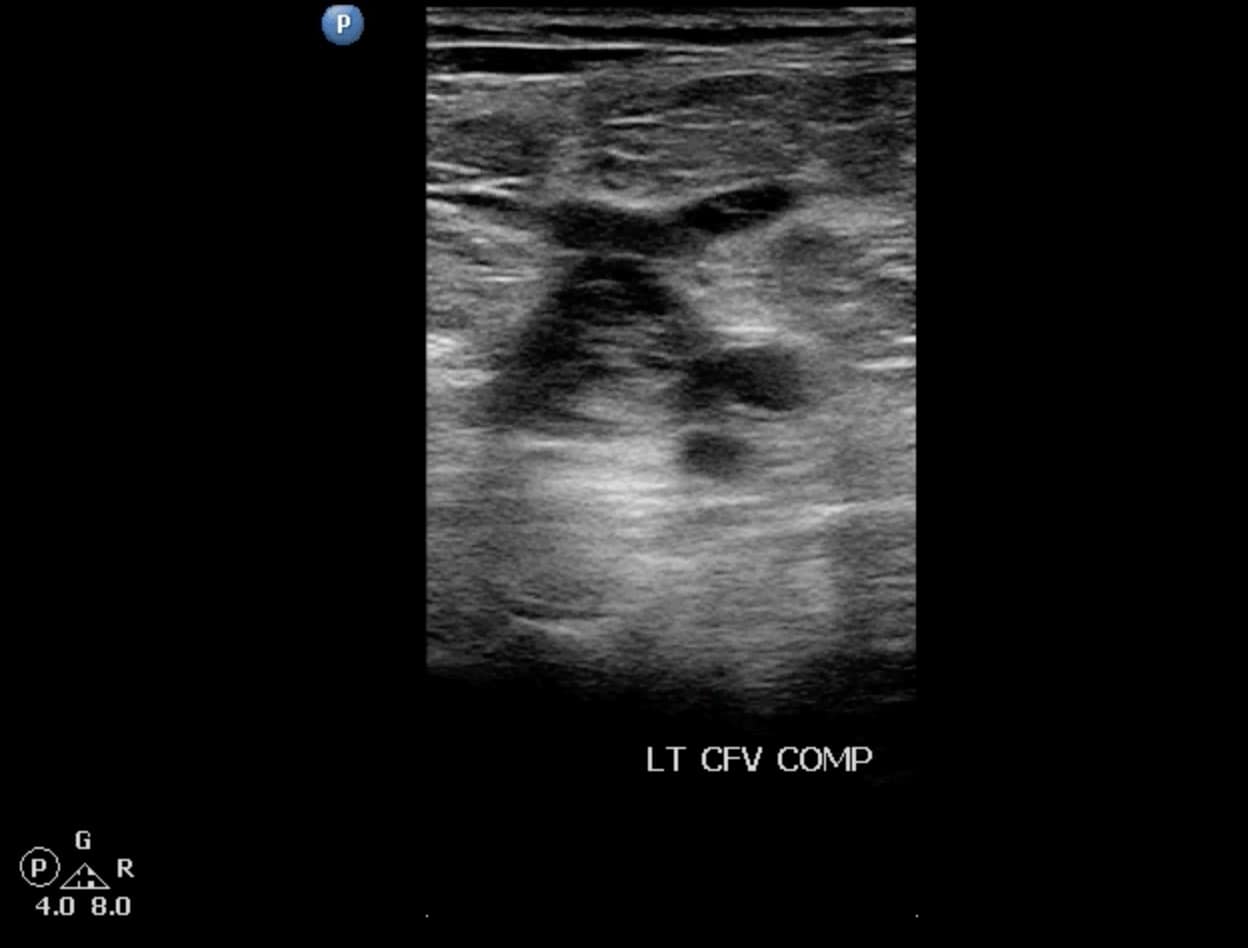

Due to its location in the pelvis, the EIV can be difficult to visualize, so the proximal protocol begins with the transducer in the transverse position high in the groin, just distal to the inguinal ligament with the CFV at the saphenous vein (SV) branch point visualized (Figure 3). A normal vein will be anechoic and easily compressible (Figure 4). Compression should be performed with the transducer transverse to the vein with compression being directed in an anterior-posterior direction. Compression should not be performed in a longitudinal plane to the vein since false-positive results can occur from “side-walling” and sliding off the vein, which can appear sonographically as a true compression. Tenting of the artery means that more than enough pressure has been applied.

Figure 3. Split screen demonstrating transverse window of common femoral vein (CFV)/greater saphenous vein (S) junction with transducer position (indicator toward patient’s right).

Figure 4. Split screen demonstrating compression of the common femoral vein (CFV) (between arrows) with transducer position shown. Note the common femoral artery (CFA) lateral to the CFV.